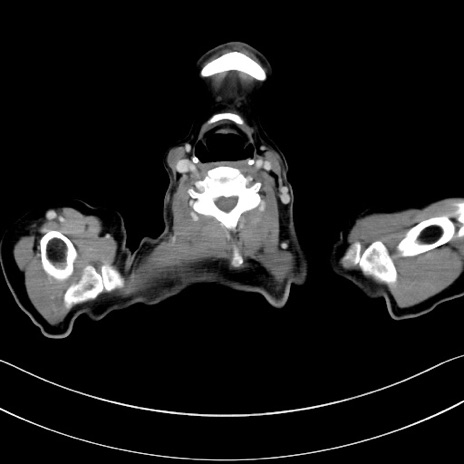

冠状断像

【症例】60歳代男性

【主訴】嘔吐

【現病歴】胃癌にて胃全摘後。食思不振が悪化し、夜中に嘔吐することがある。

【既往歴】胃癌、胃全摘、脾摘、胆摘後

【データ】WBC 5900、CRP 10.56